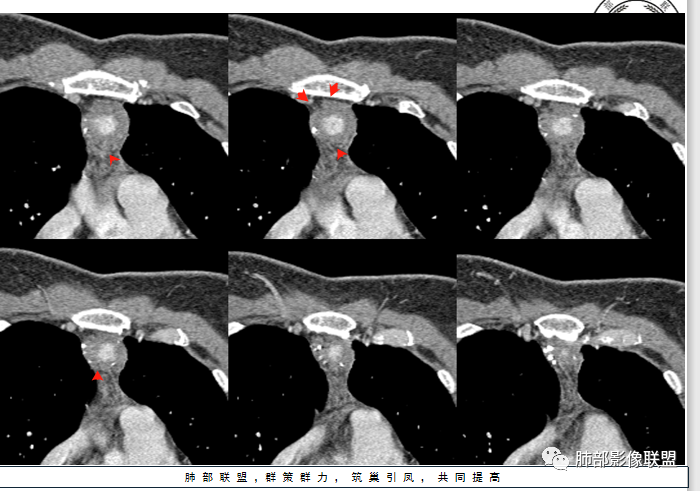

红星:女性病人48岁,前上纵隔,类圆形的实性病变,平扫密度比较均匀,周围卷见点状的钙化灶,增强扫描明显的强化, 多时相扫描中心可见跟大血管强化幅度一致的结节灶。常规胸腺瘤?鉴别血管瘤?

边缘多发条状、线样、结节状钙化

南边:边界尚清,位于残留胸腺组织内

中央结节状强化, 类似于血管强化

前纵隔海绵状血管瘤的影像学特征包括:①发生于前纵隔的圆形、类圆形、不规则肿块影,边界清晰,与邻近结构分界清晰;②CT上呈稍低密度影,内见小结节状、小片状、针尖状的钙化灶,钙化灶、静脉石影是海绵状血管瘤的特征性表现。③增强后大多数肿块可显示肿块的范围及供血情况,动脉期病灶边缘呈点片状强化,静脉期及延迟期逐步向内填充,呈渐进性强化等典型特征,部分不强化或轻度强化,部分增强 后片状强化,强化程度与邻近血管相仿;血管瘤强化方式与肿块内组织成分、血窦内血栓、血流等因素有关;Moran等研究表明,肿块强化不均匀或呈轻度强化的原因可能与扩张的血窦腔内组织平滑肌增殖及炎性纤维化有关;肿块血管样强化可提示海绵状血管瘤。前纵隔海绵状血管瘤需与畸胎瘤、胸腺瘤、胸内甲腺肿、神经内分泌肿瘤等进行鉴 别 断:①畸胎瘤多呈混杂密度影,内有脂肪、毛发、钙化灶及水样密度;②胸腺瘤呈结节状、团块状影,密度较均匀,增强后强化较均匀,与周围组织分界清晰;③胸内甲状腺肿位于前上纵隔,平扫密度常较高,可见其上端与颈部甲状腺相连;④神经内分泌肿瘤多伴坏死囊变,点片状钙化,形态常呈分叶状或 不规则形,增强后肿瘤实性部分强化显著。

综上所述,海绵状血管瘤发生在纵隔非常罕见,且缺乏典型的临床症状及特异性影像, 应从肿块的位 置、大小、形态、与周围组织的 关 系 以及CT平扫、增强特点进行分析,如前纵隔肿块内有钙化灶、静脉石、增强后点片状血管样强化及渐进性强化等特点,应考虑纵隔海绵状血管瘤的可能;薄层CT及其多平面重组有利于发现细小钙化灶,而动态增强CT扫描能更好显示肿块内血管强化,有助于术前诊断与鉴别诊断。